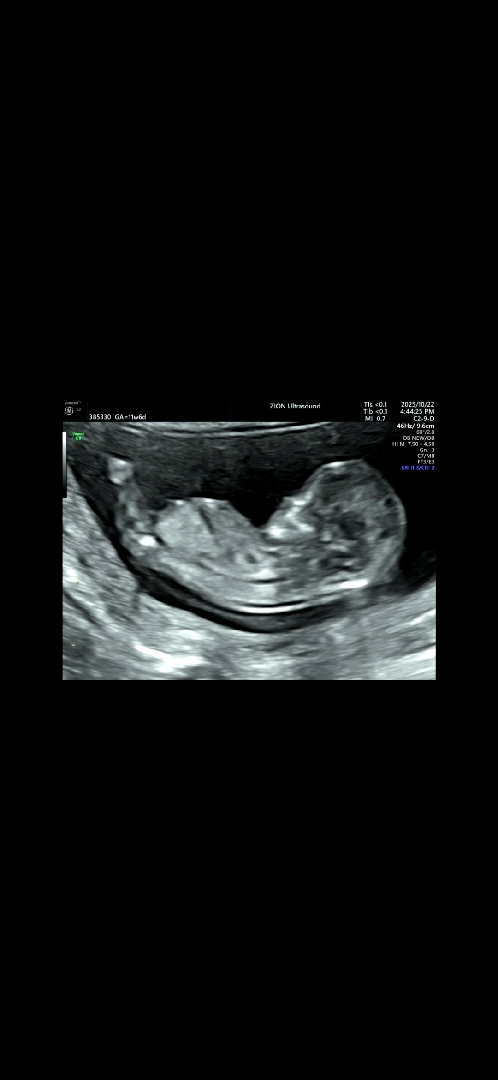

각도법 볼수 있능 사진일까요??

빌리AI는 아들이라네요 ㅎㅎ